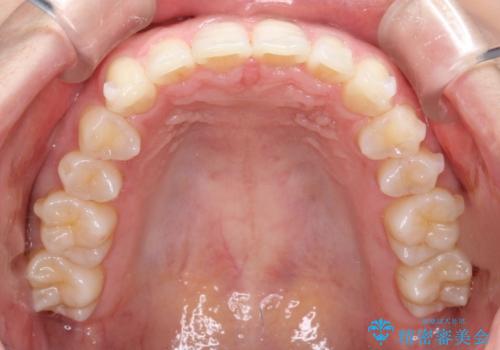

- 前歯のガタガタを綺麗にしたいとのことでインビザラインにて治療を行いました。

治療前は臼歯部反対咬合のため下顎が偏移し正中がずれていましたが、臼歯部反対咬合を改善したことで、正中のズレを改善することができました。